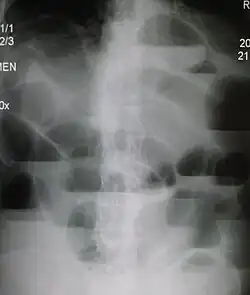

Röntgenaufnahme des Abdomens mit typischer Spiegelbildung bei Dünndarmileus

Die Röntgenleeraufnahme des Bauchs im Stehen oder in Linksseitenlage zeigt beim typischen Ileus überblähte Darmschlingen mit Flüssigkeitsspiegeln als Hinweis auf den Ort eines Verschlusses. Je nach Befinden können durch einen Einlauf und/oder eine Passage mit Kontrastmittel Ort und Ursache eingegrenzt werden.